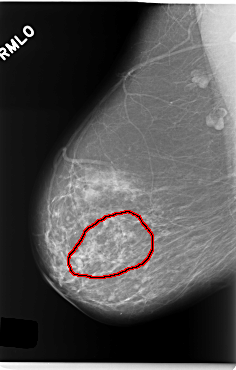

C_0214_1.RIGHT_MLO

RIGHT_MLO LINES 5912 PIXELS_PER_LINE 3776 BITS_PER_PIXEL 12 RESOLUTION 50 OVERLAY

FILE: C_0214_1.RIGHT_MLO.OVERLAY

TOTAL_ABNORMALITIES 1

ABNORMALITY 1

LESION_TYPE CALCIFICATION TYPE PLEOMORPHIC DISTRIBUTION SEGMENTAL

ASSESSMENT 4

SUBTLETY 4

PATHOLOGY MALIGNANT

TOTAL_OUTLINES 1

BOUNDARY